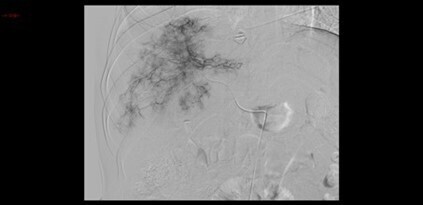

Le traitement suivant est par la suite réalisé.

Question 12 - À quoi correspond ce traitement (une ou plusieurs réponses exactes) ?

L’embolisation vasculaire radioguidée (artériographie) est la technique privilégiée pour le traitement des hémorragies abdominales en urgence. Elle consiste, après ponction artérielle, à la cathétérisation du vaisseau responsable du saignement, le plus sélectivement possible, et l’injection de matériel embolisateur.

La première figure montre bien la flaque artérielle du produit de contraste (saignement actif artériel) au niveau du segment V.

La seconde figure, elle, correspond au contrôle en fin de procédure après embolisation de la branche artérielle hépatique responsable du saignement, montre la disparition de cette flaque.